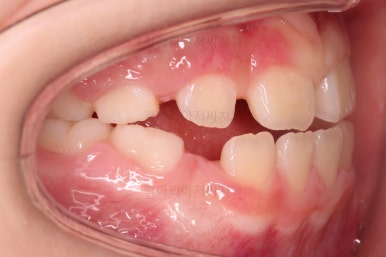

초진 시 입안의 모습입니다.

아래쪽 치열이 전반적으로 윗니보다 앞쪽에 위치한 전형적인 앵글씨 3급 부정교합인데요.

어금니에서부터 앞니까지 아랫니가 윗니보다 앞쪽에 위치하네요.

특히 앞니는 아랫니가 윗니보다 나와있는 "반대교합" 상태였고요.

또한 위아래로 겹침이 없고 떠있는 "개방교합" 상태였어요.

즉, 앵글씨 3급 부정교합 - 반대교합 - 개방교합 등 굉장히 복합적인 교합의 문제를 가진 환자였습니다.